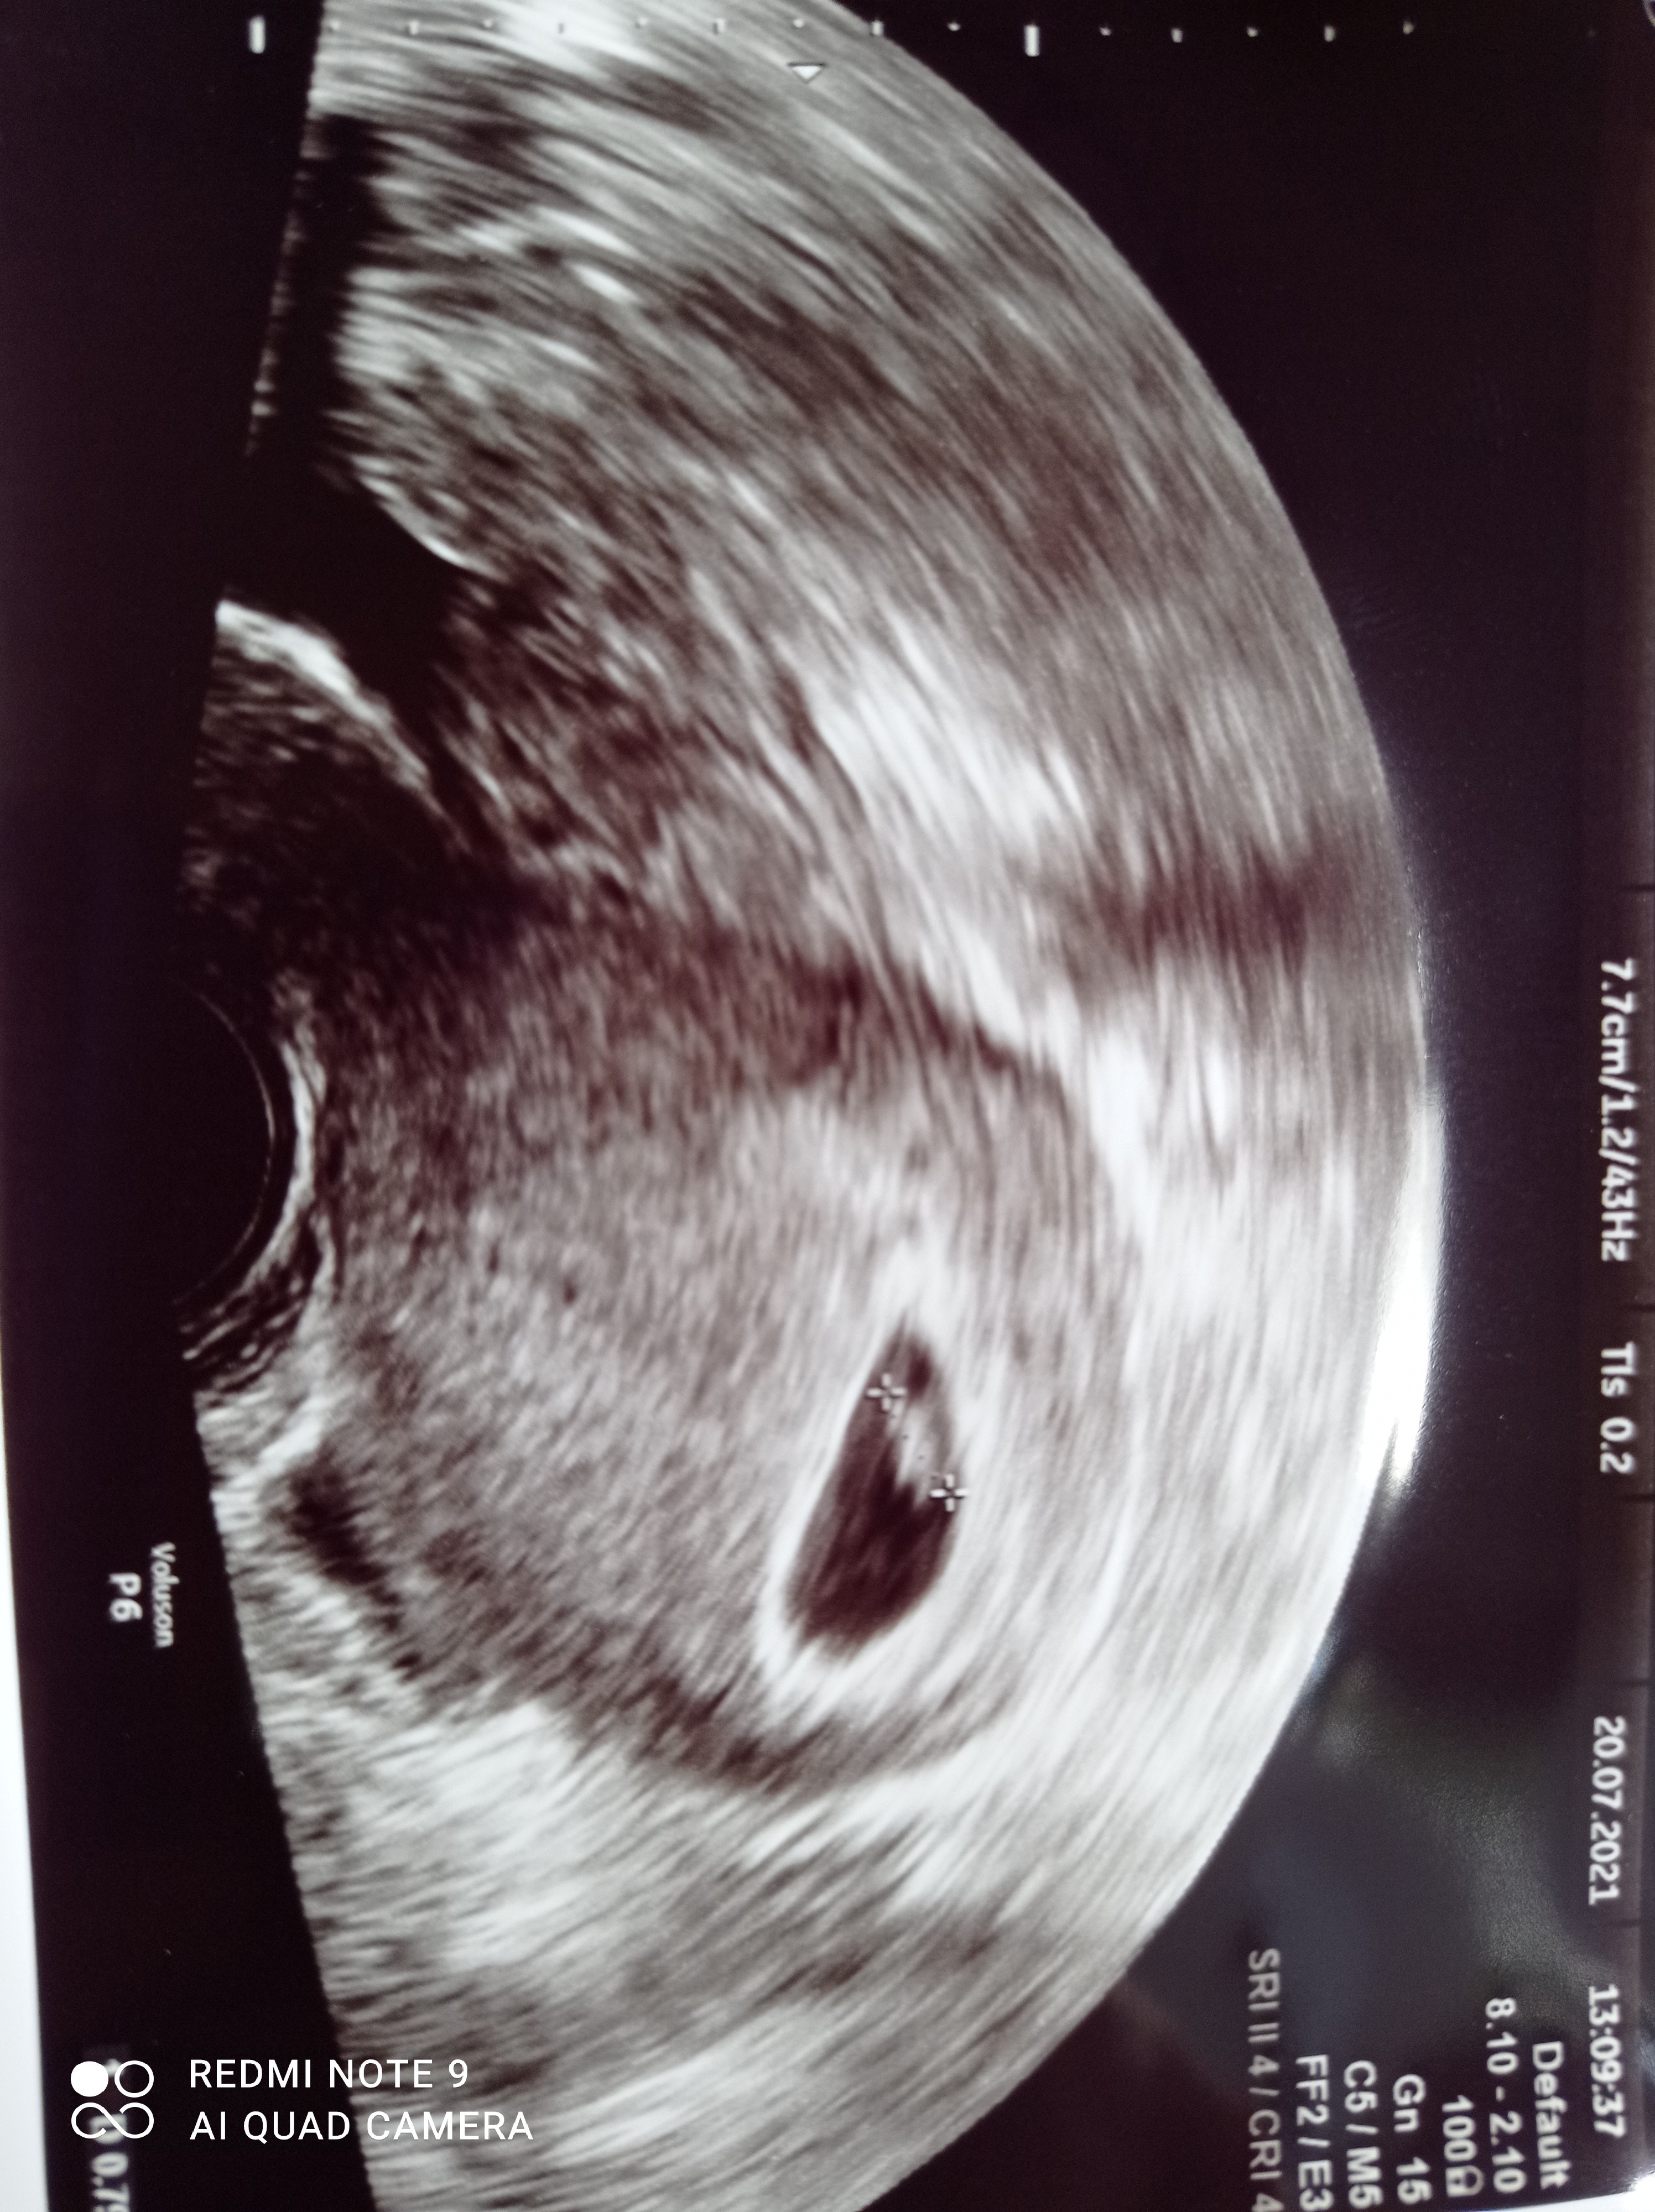

Ale super mamy kolejnego maluchaJa już też jestem po wizycie, jest wszystko dobrze, kijanka ma 8mm i już bijeWedług OM 6+2, według USG 6+6